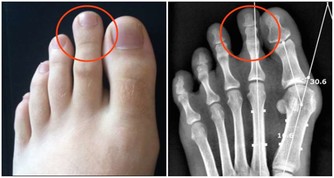

雞眼極為常見,多數人都見過。雞眼也很好治,一般的藥店有雞眼膏,自己貼上就能治好;但有很多人雞眼治了很久沒好,反而越長越多的,影響美觀又不健康。

雞眼是足部皮膚局部長期受壓和摩擦引起的局限性、圓錐狀角質增生。俗稱「肉刺」。長久站立和行走的人較易發生,摩擦和壓迫是主要誘因。